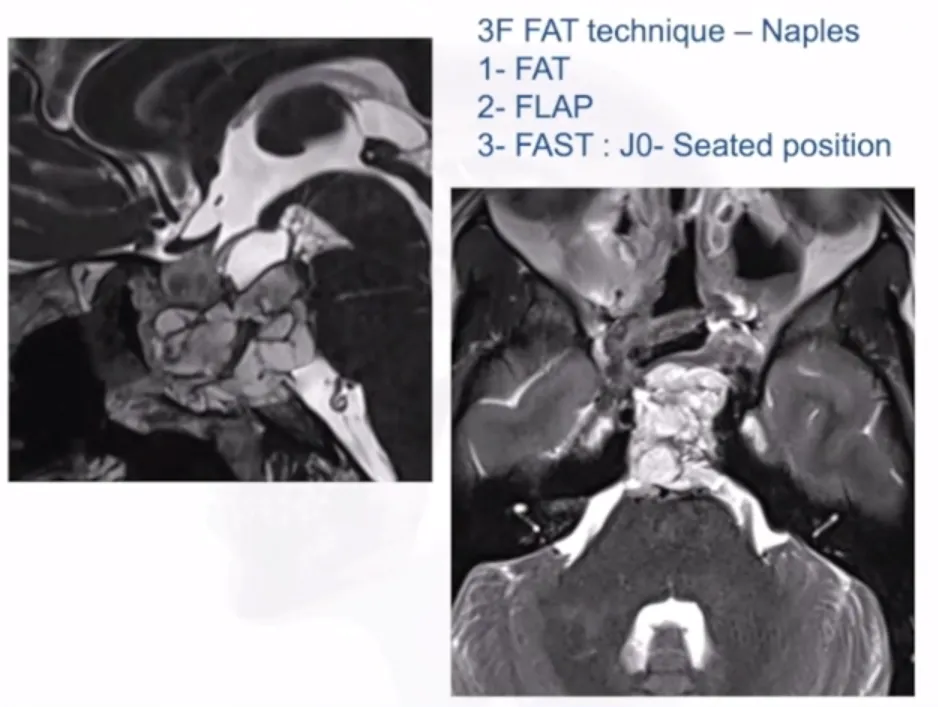

4、3F技术(Fat,Flap,Flash):1、自体脂肪填充;2、皮瓣闭合;3、尽可能快地保持患者直立的姿势,以降低颅内压。有效降低脑积液发生率